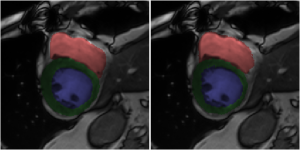

Fig. 3 shows consistent accuracy for the segmentation of all anatomies ({LV,RV,Myo} at {ED,ES}) over a large range of values for . In terms of DSC, Myo is the hardest anatomy to segment, while regarding Hausdorff distance, RV appears to be challenging because of the sensitivity of this distance measure to outliers. These results are around to worse than the best ones in the ACDC challenge [5]. However, no direct comparison can be made with the ACDC challenge results [5] as we did not obtain results on the test set because of the inference approach described in Sec. 2.4 consisting of the assessment of the six central slices per volume.

The bottom row of Fig. 3 shows the segmentation results along with their ground truth for and , where three out of twenty-five cases are misdiagnosed (we show two correct and one incorrect diagnosed case). For the case that has been incorrectly diagnosed in Fig. 3 (rightmost image, ARV misclassified as NOR), the shown under-segmented RV segmentation is representative of the entire ES phase, while for the ED phase, the RV is correctly segmented. Given that ARV relies on RV ejection fraction, such mistake in the segmentation would suggest adequate myocardial contraction and explain why this case is classified as normal. This mistake provides evidence that the features used for training the classification parameters may be strongly correlated with segmentation accuracy. The other two misclassifications involve scans that have imaging artifacts near the heart, similar to the middle image in the bottom row of Fig. 3. Interestingly, the only four cases in the validation set that contain imaging artifacts have a softmax probability (i.e., classification confidence) of around 0.7, while all other scans have a probability near 1. Segmentation performance is unaffected by such artifacts, and two of these four cases are still correctly classified, but it does show that classification performance suffers in scans with imaging artifacts.